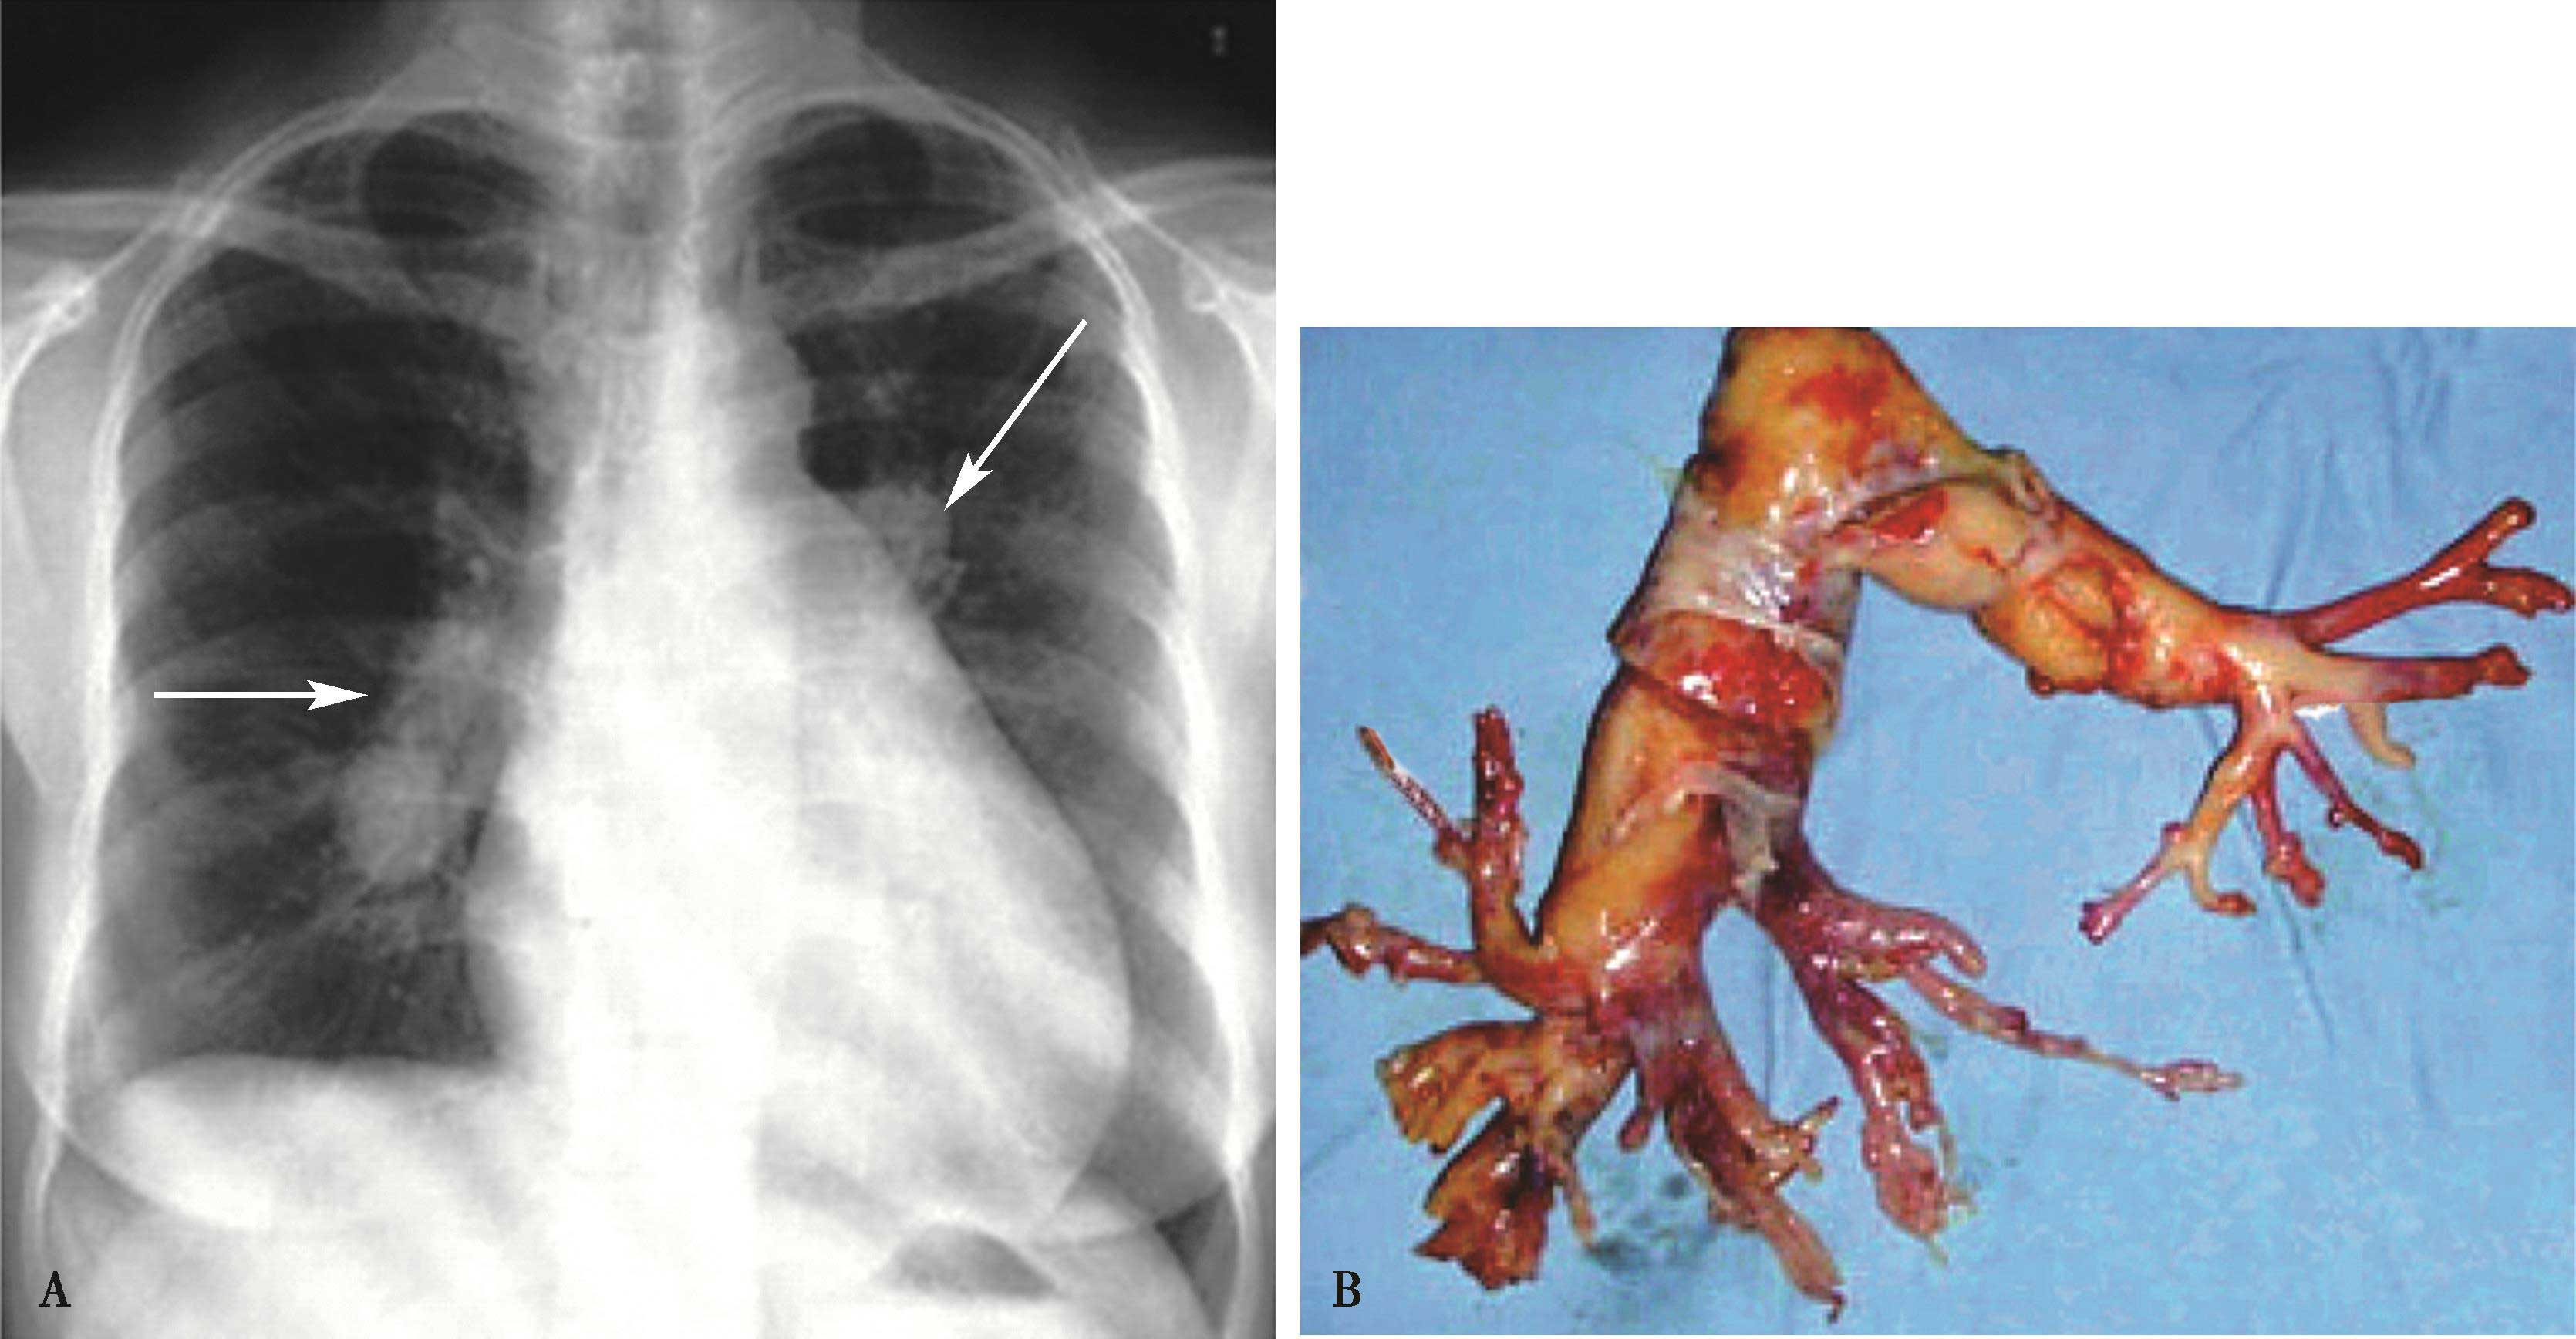

图7-2-2 女,39岁,气短,左手无脉。ECG:RVH;X线片(A)示两侧肺血不对称,右侧肺血少,右下肺动脉纤细(▲);左侧肺血多(↑);肺动脉段凸,右心增大,肺动脉高压。X线片诊断:大动脉炎 “肺动脉型”,肺动脉高压。诊断经造影证实(B)